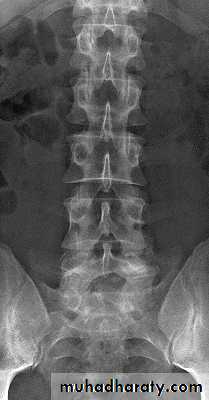

Lumbar Spine X Ray

A/P radiograph• Sacrum